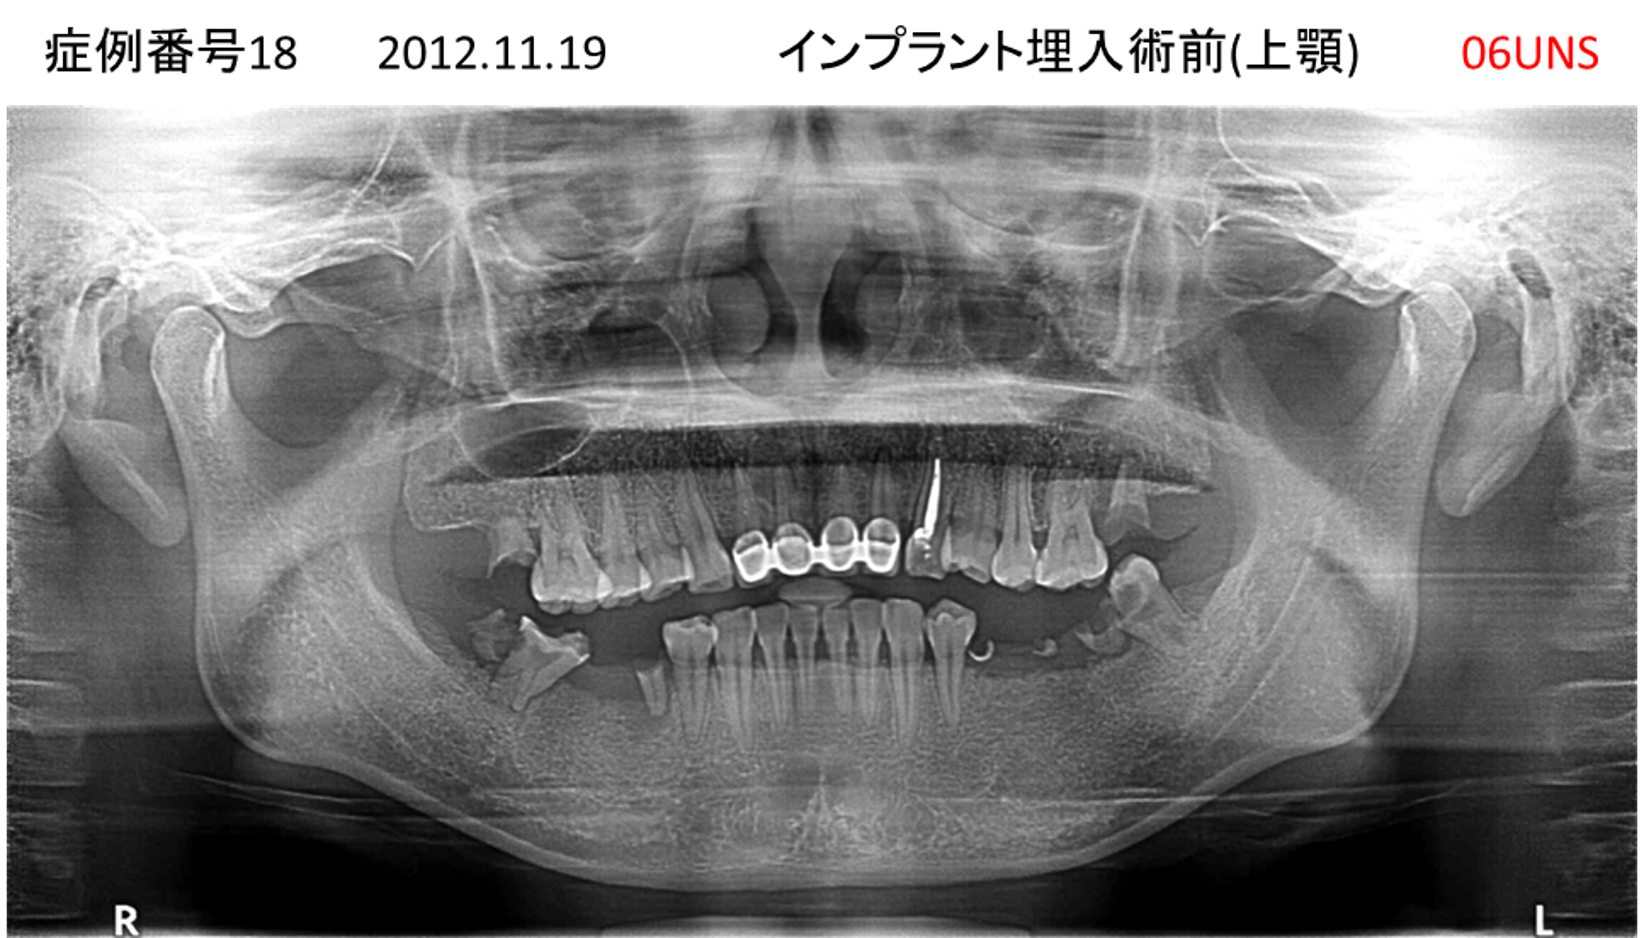

上の前歯が揺れてきてかめない患者様のインプラント症例

| 治療名称 |

インプラント |

| 治療費用 |

440万円+税 |

| 治療期間 |

6か月 |

| 患者さんの症状(主訴) |

上の前歯が揺れてきた。かめない |

| 治療内容 |

サイナスリフト、GBR、インプラント、即時荷重 |

| 治療結果 |

上の前歯の揺れが収まった。奥歯でしっかり噛める。 |

| 治療の注意点(リスク/副作用) |

インプラントが壊れたら再治療が必要 |